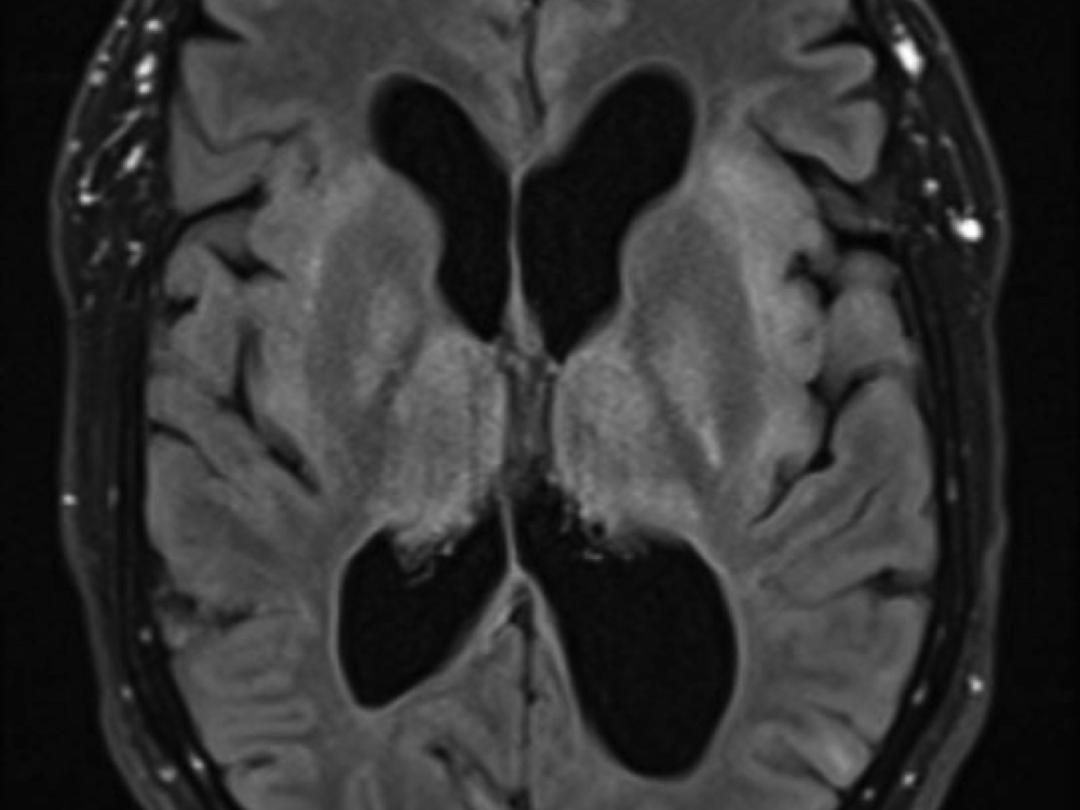

We beschrijven een 48-jarige man die op de SEH kwam met koorts, malaise, afwerend gedrag en een verminderd bewustzijn (E4M5V2) bij een influenza A-infectie. Nadien ontwikkelde hij een insult, waarvoor intubatie en opname op de afdeling Intensive Care noodzakelijk was. Bij een persisterend comateuze toestand (E1M1V1) werd uitgebreide diagnostiek verricht. Op basis van passende neurologische symptomen, traag achtergrondpatroon op het elektro-encefalogram, klassieke bilaterale afwijkingen in de thalamus en basale kernen met necrose op de MRI en een microbiologisch bewezen infectie van het centraal zenuwstelsel door influenza A werd de diagnose ‘influenza-geassocieerde acute necrotiserende encefalitis’ gesteld.

Acute necrotiserende encefalitis is een ernstige complicatie van een veelvoorkomende infectie. Geadviseerd wordt om bij patiënten met een influenza-infectie en neurologische symptomen, zoals insulten, verwardheid of coma, te overwegen om vroegtijdig te beginnen met beeldvormend onderzoek met MRI en behandeling met corticosteroïden.